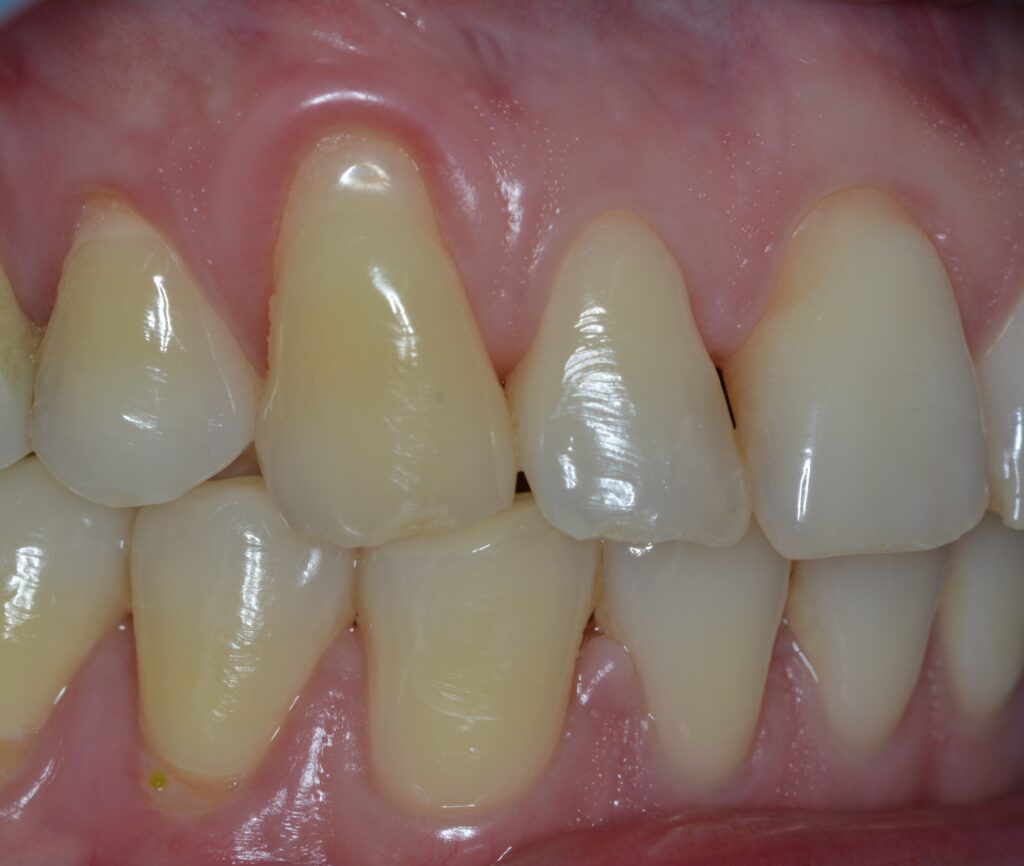

Retração ou Recessão Gengival é o que ocorre quando a margem gengival migra em direção apical (ponta da raiz) deixando raiz exposta.

O surgimento de uma Retração Gengival normalmente ocorre por uma interação de fatores, de forma que temos fatores predisponentes (ausência de Gengiva Queratinizada, má posição dentária, tração de freios e bridas, etc) e fatores desencadeantes (escovação traumática, Coroas desadaptadas, inflamação, trauma oclusal, fumo, etc).

Sinais e Sintomas

Pode ocorrer em um único dente;

Pode ocorrer em vários (Múltiplas)

Aspecto antiestético;

Maior facilidade de desenvolver cárie radicular;

Aumento da Sensibilidade a alterações de Temperatura.

Exame Radiográfico

O exame Radiográfico é muito importante, deve ser observado o volume e a posição da crista óssea para que se tenha uma melhor condição de previsibilidades, viabilidade e escolha da técnica a ser utilizada. (RX Periapical e Interproximal)